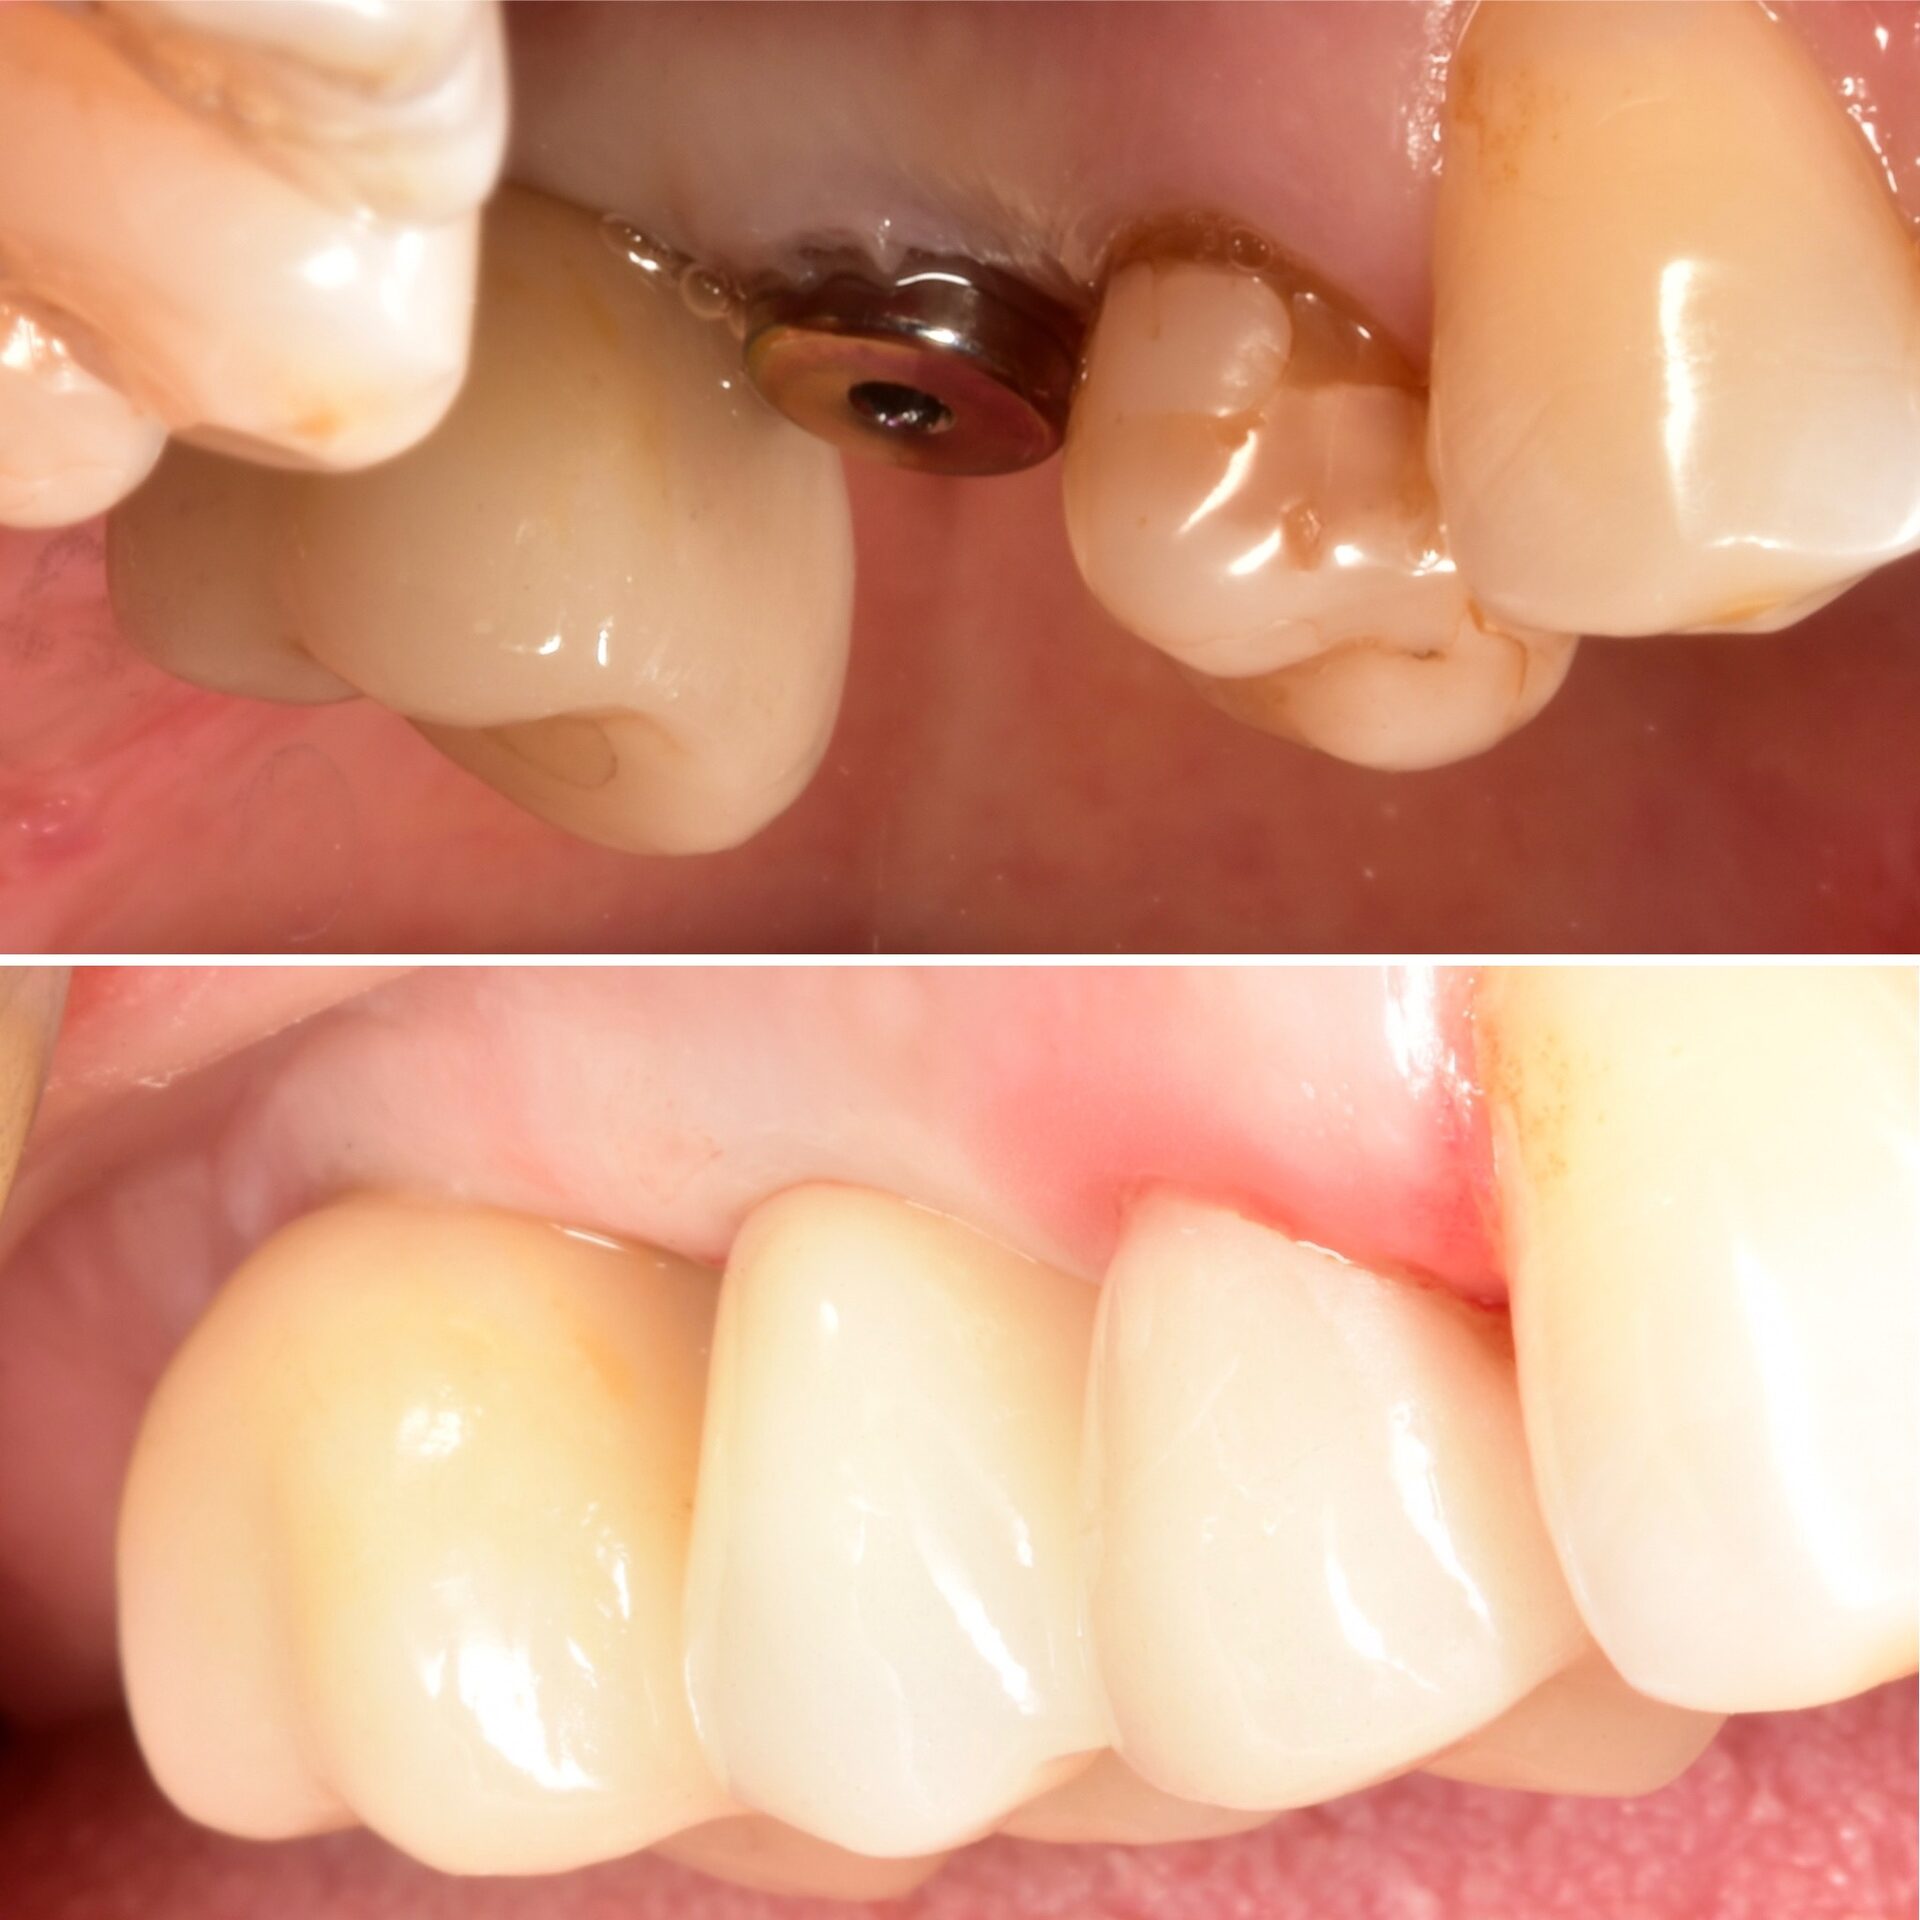

Керамическая коронка на имплантате